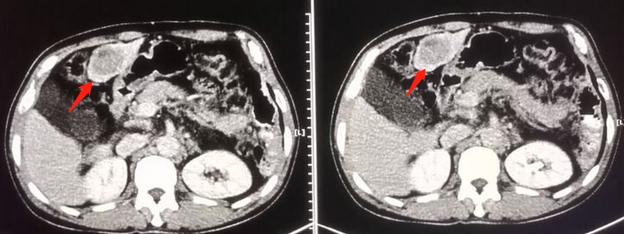

下面是另一个长期生存的病例:

男性,51岁,乙肝多年,乏力、腹痛1个月,肝左叶肝癌

肝动脉化疗栓塞术后5年,无复发征象。但患者肝硬化进展,肝功能减退,出现少量腹水